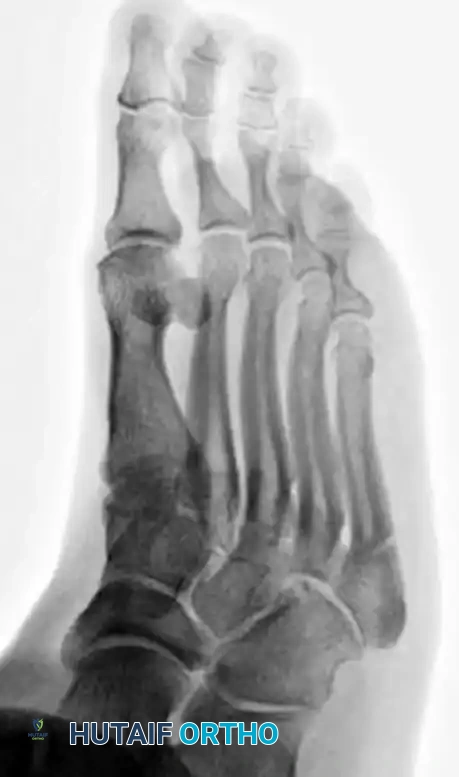

PREOPERATIVE PLANNING AND IMAGING

Standard weight-bearing anteroposterior (AP), lateral, and oblique radiographs of the foot are mandatory. The oblique view is particularly useful for profiling the fracture line at the metaphyseal-diaphyseal junction.

In cases of delayed union or nonunion, advanced imaging such as a Computed Tomography (CT) scan may be warranted to assess the extent of medullary sclerosis and to precisely measure the canal diameter. The medullary canal of the fifth metatarsal is not perfectly straight; it exhibits a lateral and plantar bow. Preoperative templating is critical to select a screw diameter that achieves cortical purchase without causing iatrogenic lateral cortical blowout.

- Verify final screw placement, fracture reduction, and compression with orthogonal radiographs.